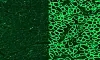

Bildet illustrerer hundenes muskelceller før og etter behandlingen. [Illustrasjon: UT Southwestern]

Noen uker etter at hundene hadde fått behandlingen, var det manglende proteinet dystrofin kommet tilbake. Hundenes muskelfunksjon ble bedret med alt fra 3 til 92 prosent, avhengig av hvilke muskler forskerne så på.

To grunnleggende funksjoner ble vesentlig bedret etter behandling: Hjertemusklene fungerte 92 prosent bedre, og muskler som er viktig for pust styrket seg med 58 prosent.